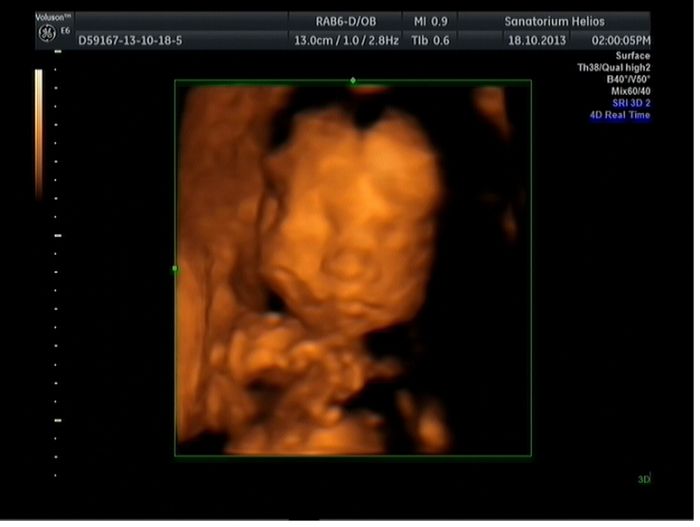

Naše malá (velká - i pan doktor se diví, jak rychle roste, za začatku to vpadalo, že bude malušenká a teď už je snad týden a něco napřed)tlačí snad všude. Doktor ale říká, že je to tím, že jsme jako rodiče, oba dva velcí. Mám takový dotázek, doktor nás posílá na 3-tí velký ultrazvuk v 30 týdnu, co nás tam může čekat? Myslela, jsem, že všechny vyšetření jsou už za námi?